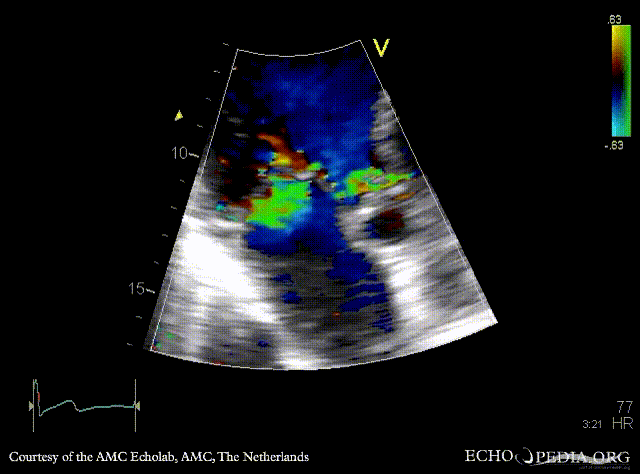

A3CH: Color Doppler, severe aortic regurgitation, excentric jet Continuous-wave signal of severe aortic regurgitation